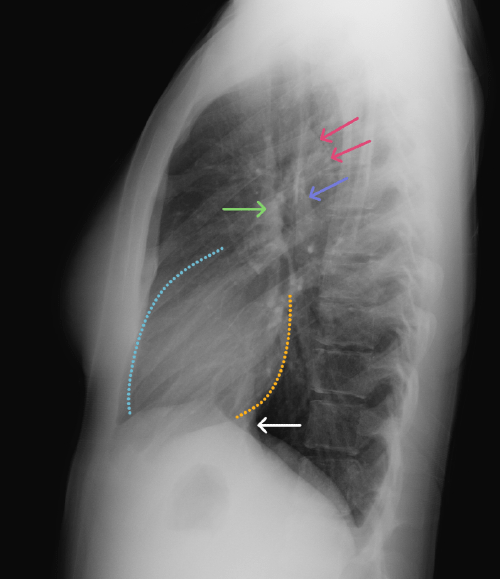

Labelled radiographs and CT/MRI series teaching anatomy with a level of detail appropriate for medical students and junior residents.

Chest

Chest

Chest radiograph & CT anatomy

Chest

Chest

Chest radiograph & CT anatomy